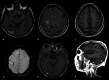

A MRI and FLAIR T2W images. Cortical and subcortical high T2 signal in the posterior right temporal lobe corresponding to arterial infarct B High T2 signal subcortical in the frontal lobe corresponding to venous infarct C T1W axial view. High subcortical signal due to hemorrhage in venous infarct. D SWI linear low signal corresponding to thrombosed cortical frontal vein. E Axial T1W with gadolinium. Cortical and meningeal enhancement typical of an arterial stroke. F Sagittal T1W with gadolinium. Intrinsic T1 enhanncement of the thrombosed frontal vein and in cortex of the posterior cortical temporal stroke